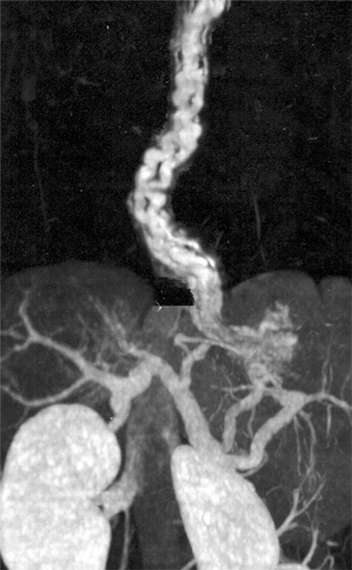

症例画像2:3D-CT angiography(volume rendering法)

出典

img

1: 著者提供